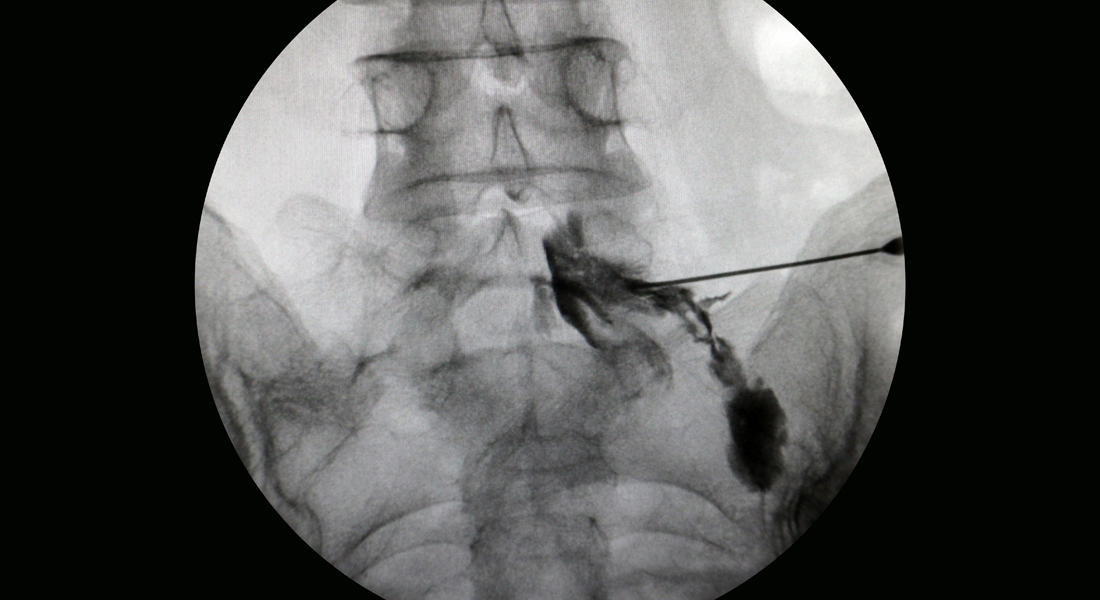

특수 카테터로 좁아진 척추관을 확장시켜 치료하는 비수술 요법

추간판 탈출로 신경이 압박되는 부분에 풍선 확장 기능이 포함된 특수 카테터를 이용하여 주변을 확장시켜 압박을 해소하고 통증을 없애는 치료법입니다. 확장과 함께 증상 호전에 도움이 되는 약물을 주입하여 효과적으로 통증을 완화할 수 있습니다.